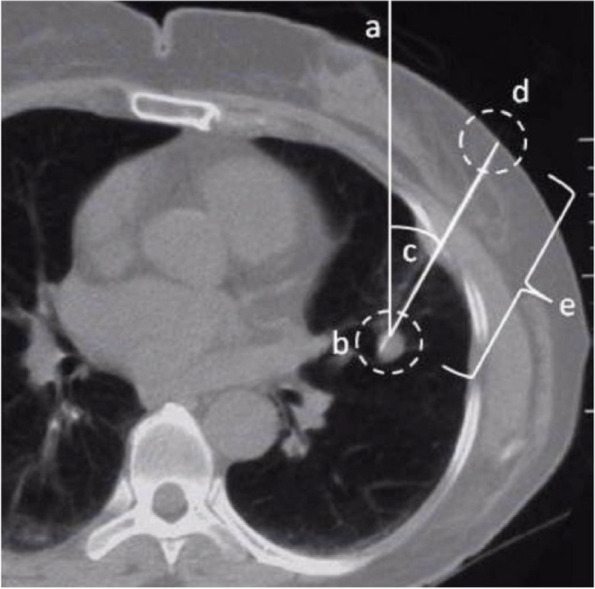

Fig. 6.

In the image a cross section of a human thorax is shown. a True vertical of the CT coordinate system, b target, c angle with respect to the vertical line, d entry point, e depth